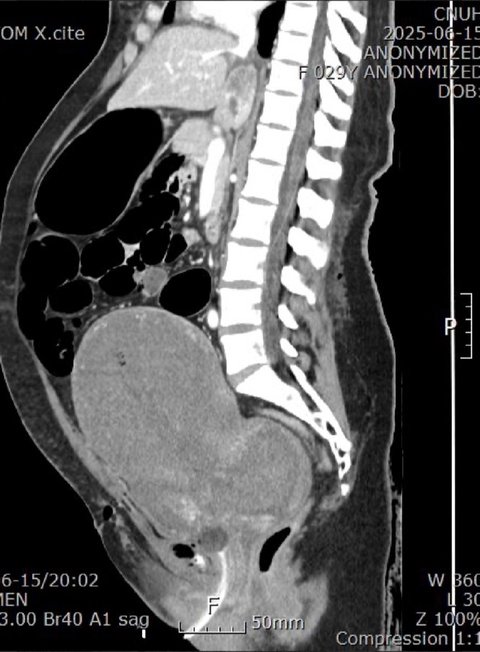

* (+추가) 사진을 보시면 경막외마취를 할 경우 파랑색 선 대로 카테터가 들어가야 하지만, 빨간색 처럼 카테터가 들어가 척추 마취가 된 것입니다. 이 사진은 언니가 이송 된 대학 병원 교수님께서 설명해 주신 부분입니다.

* 참고로 척추 마취에는 경막외마취에 비해 약물 용량이 1/10 수준으로 적어야 하며, 뇌로 약물이 흘러 들어가지 않도록 반드시 상반신을 세운 상태에서 진행하거나, 기관삽관을 병행해야 한다고 합니다.

하지만 언니의 경우 경막외마취를 하고자 했기에 이러한 사전조치 없이 척추마취가되어 호흡 불가 및 심정지에 이른 것이 아닌지 의문이 듭니다.